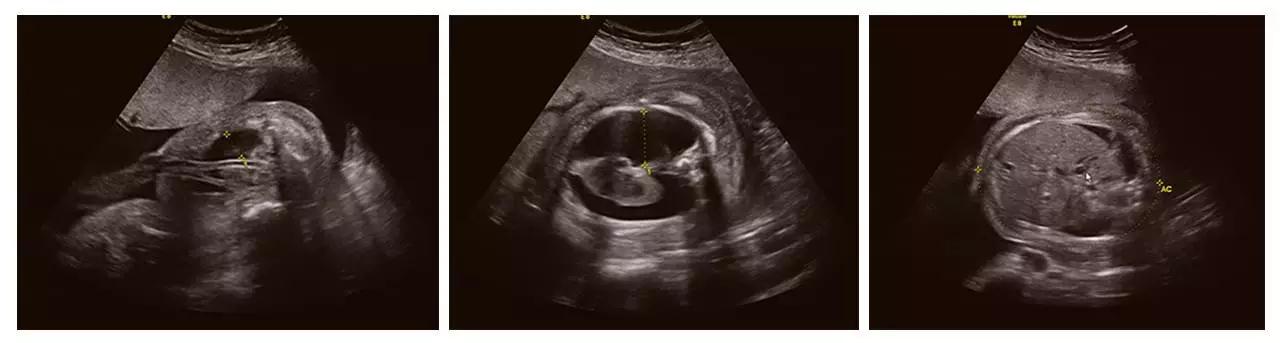

宝宝的健康是妈妈最大的牵挂。据了解,我国是出生缺陷高发的国家之一,每年约有80-120万缺陷儿出生。目前产前筛查的主要手段是超声检查,尤其是四维彩超(四维彩超),诊断胎儿结构异常的准确率可达95-98%。

济南艾玛妇产医院引进的GE高清四维彩超(四维彩超)设备,是目前世界上先进的彩色超声设备,远比普通超声设备清晰、准确,被誉为"神奇彩超",是产前筛查的尖端设备,能够多方位、多角度地观察宫内胎儿的生长发育情况,为早期诊断胎儿先天性体表畸形和发育异常提供科学依据,以便尽早的进行治疗。有效防止和减少新生儿出生缺陷的发生。

成功筛查胎儿畸形的案例(部分)

(右手多指畸形)

(单侧唇裂)

(双侧唇裂)

(左心发育不良)

(胸腹腔积液、全身水肿)

(颈后水囊瘤)

(胎儿左手未见,考虑截肢畸形)

(胎儿颅内结构异常、眼距窄、鼻结构异常...)

以上案例更多的是警示我们四维彩超(四维彩超)检查的重要性。我们希望每一个宝宝都能健康成长。

把握做四维彩超(四维彩超)的最佳时间

四维彩超(四维彩超)检查的适宜时间是孕期22-26周。此时胎儿大小及羊水适中,活动度大,体表也比较丰满,利于胎儿超声成像和胎儿畸形筛查。孕妈们一定要注意四维彩超(四维彩超)检查的最佳时间,提前做好预约准备哦。(点阅读原文可咨询预约)